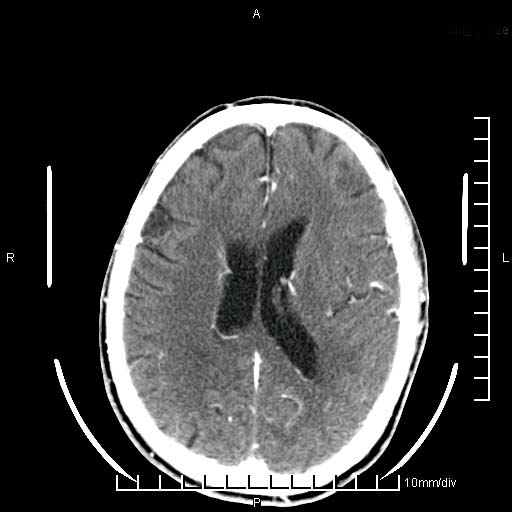

临床以双下肢浮肿,疼痛收治,无明显神经系统症状,既往无梗塞,出血病史。左颞叶见低密度灶,考虑什么?

无强化、 无占位、局部脑沟增宽, 软化灶吧。